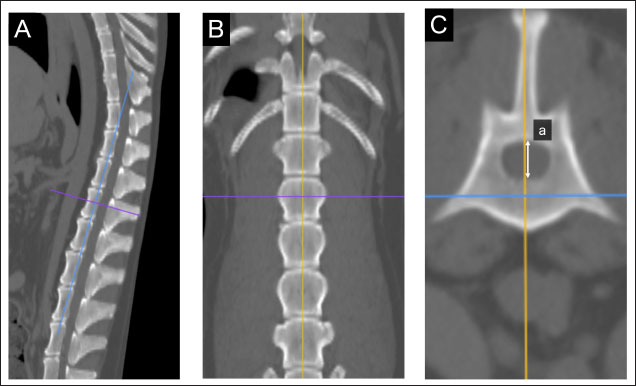

In the sagittal and dorsal sections, the crosshairs were adjusted to be parallel to the maximum diameter of the adrenal gland (Fig. 1A and B). The crosshairs showed the slice position in the other two panels of Figure 1. A transverse section that includes the maximum diameter was created; the maximum diameter parallel to the section plane was defined as the major axis, whereas the maximum diameter perpendicular to the section plane was defined as the minor axis (Fig. 1a–c). The major axis of the adrenal gland was defined as the longest dimension in the transverse plane (Fig. 1b), and the dimension of the minor axis was defined as the length perpendicular to the major axis in the same plane (Fig. 1c). The major and minor axes of the adrenal glands were measured using three-dimensional multi-planar reconstruction (3D-MPR) and a soft-tissue algorithm (window level: 40, window width: 250) (Fig. 1A–C).

Fig. 1. Method used for measuring minor axes of the bilateral adrenal glands. In the sagittal (A) and dorsal (B) sections, the crosshairs were positioned to be parallel to the maximum diameter of the left adrenal gland (a). The crosshairs show the slice position in the other two panels. The transverse section including the maximum diameter (a) is created. (C). The maximum diameter is defined as the major axis (b) parallel to the section plane, and the maximum diameter perpendicular to (b) is defined as the minor axis (c).